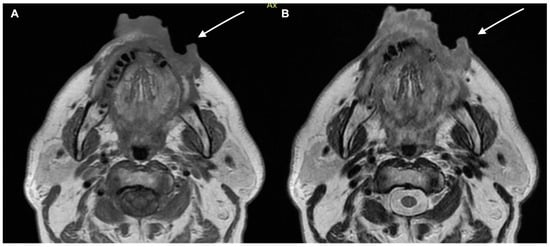

- Kawaguchi, M.; Kato, H.; Suzui, N.; Miyazaki, T.; Tomita, H.; Hara, A.; Matsuyama, K.; Seishima, M.; Matsuo, M. Imaging findings of cutaneous angiosarcoma of the scalp: Comparison with cutaneous squamous cell carcinoma. Neuroradiol. J. 2021, 34, 329–334. [Google Scholar] [CrossRef]

- Kawaguchi, M.; Kato, H.; Tomita, H.; Hara, A.; Suzui, N.; Miyazaki, T.; Matsuyama, K.; Seishima, M.; Matsuo, M. Magnetic Resonance Imaging Findings Differentiating Cutaneous Basal Cell Carcinoma from Squamous Cell Carcinoma in the Head and Neck Region. Korean J. Radiol. 2020, 21, 325–331. [Google Scholar] [CrossRef] [PubMed]